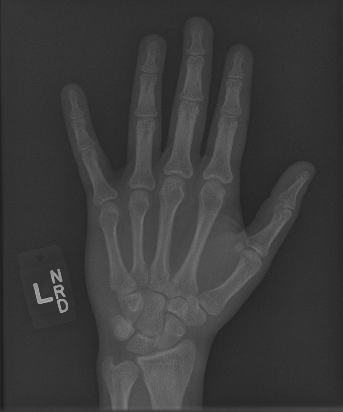

In this work, we focus on a subset of the MURA dataset [17] containing only hand images. In total, we have 5,543 images of 2,018 studies of 1,945 patients. Each study is labeled as negative or positive, where positive means that there was an anomaly diagnosed in this study. There are 521 positive studies, with a total of 1,484 images. Figure 1 shows some examples from the dataset. In summary, our contributions are as follows: